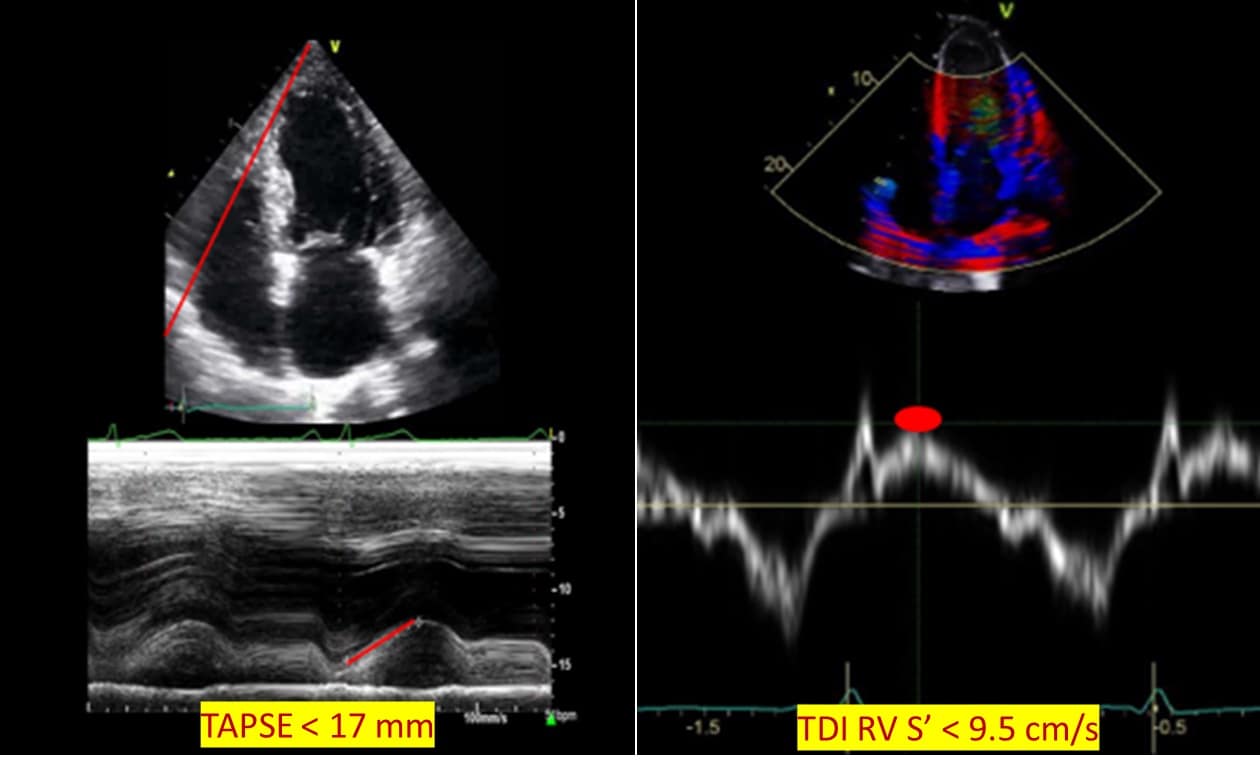

TAPSE is the systolic displacement of the tricuspid annulus towards the RV apex measured at peak systole using M mode. A value of TAPSE < 17 mm is the most validated surrogate for RV systolic dysfunction function due to high inter-rater and intra-rater reliability. 10 An TDI RV S’, another marker routinely used to assess for RV injury, measures the peak systolic myocardial velocity of the tricuspid annulus. TDI RV S’ velocity < 9.5 cm/sec is consistent with RV systolic dysfunction. 8 Alternatively, sTAPSE (subcostal TAPSE) and subcostal echocardiographic assessment of tricuspid annular kick have been suggested for use in patients with challenging apical views.14 (Figure 4)

Figure 4: Regional right ventricular systolic function.

TAPSE = tricuspid annular plane systolic excursion, TDI RV S’ = Tissue Doppler imaging: right ventricular lateral tricuspid annulus peak systolic velocity